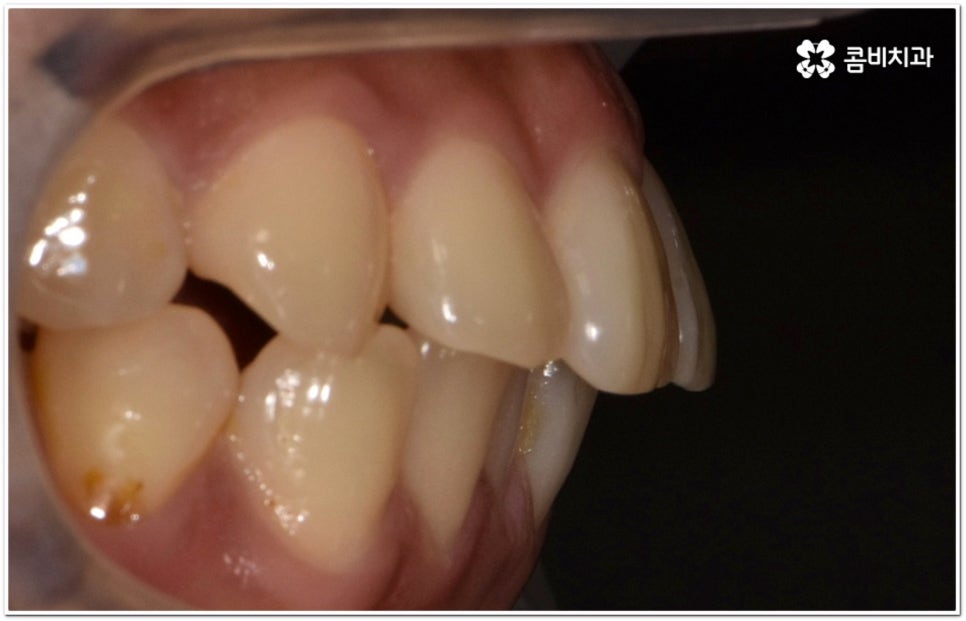

이때 위아래 치아가 맞물리는 데는 별다른 문제가 없고 앞니 등 치아가 조금 뻐드러진 상황이라면 각도만 개선해도 되지만 잇몸뼈 자체가 나와 있고 교합에도 문제가 있다면 종합적인 해결이 필요할 수 있는데요.

단순히 치아가 튀어나온 각도를 고친다고 돌출입 개선이 되지는 않고 구조적 골격적인 원인을 파악하여 해결해야 추후 턱관절 건강 부분에까지 좋지 않은 영향을 미치는 것을 막을 수 있습니다.

말씀드렸던 것처럼 돌출입의 원인이 치아 만의 문제, 즉 각도가 살짝 앞으로 뻐드러진 데 있고 상태가 그다지 심한 것 같지 않다면 보다 빠르고 간편한 수복이 가능할 수 있어요. 튀어나온 부분을 집어넣기 위해서는 발치가 필수적이지 않을까 생각하실 수 있는데 후방으로 이동시켜 줄 공간이 충분하다면 치간 삭제, 악궁 확장, 어금니 후방 이동 등 다른 방법을 이용하여 비발치 치료 과정을 진행할 수 있으므로 너무 걱정하지 않으셔도 될 거예요. 오히려 환자분들의 다양한 상황을 고려하지 않고 무리하게 발치 교정을 진행하게 되면 옥니나 합죽이와 같은 부작용이 일어날 수도 있기 때문에 원인을 정확하게 파악하고 적절한 치료를 할 수 있도록 임상 경험이 풍부하고 뛰어난 노하우를 가지고 있는 숙련된 의료진에게 교정 치료를 맡기시는 것이 굉장히 중요하다고 할 수 있습니다.